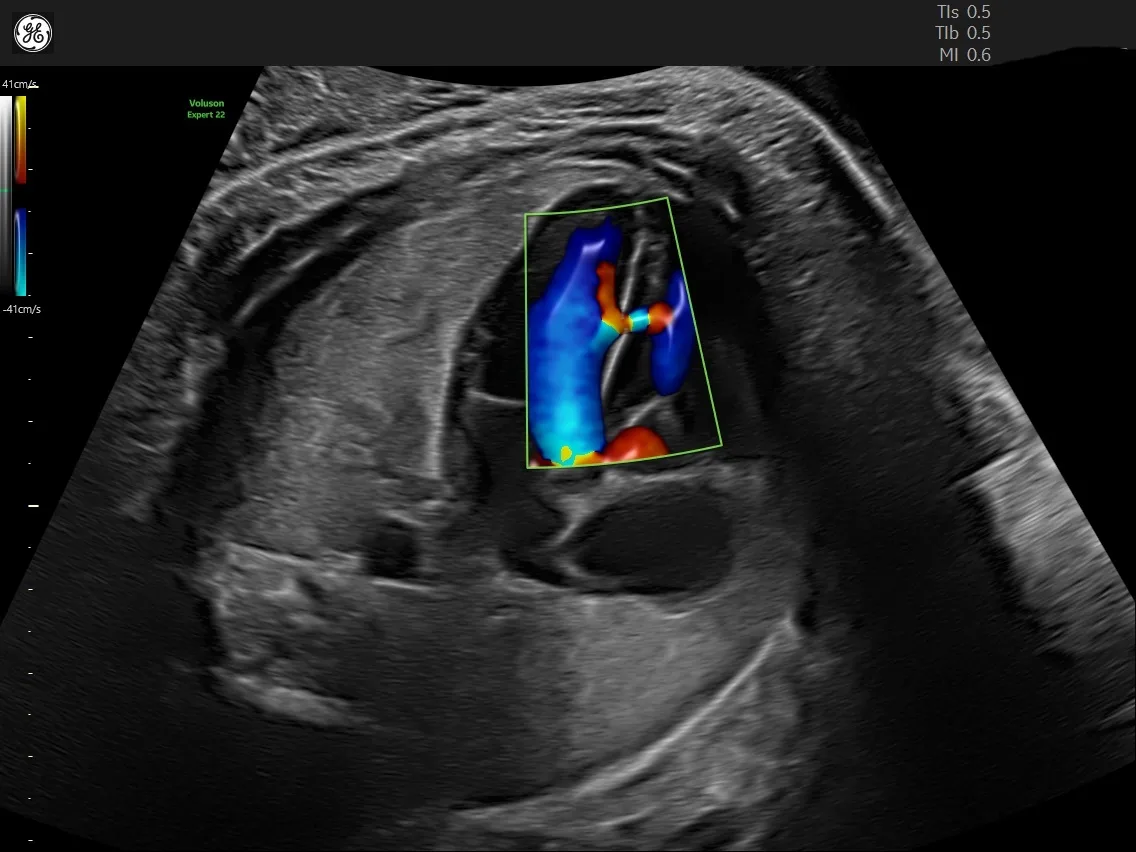

Child care begins at the fetal stage, and sophisticated fetal ultrasonography is used to track the health of an unborn child. We provide thorough evaluations and finely detailed photographs using the most recent technology to track your baby's growth and well-being.